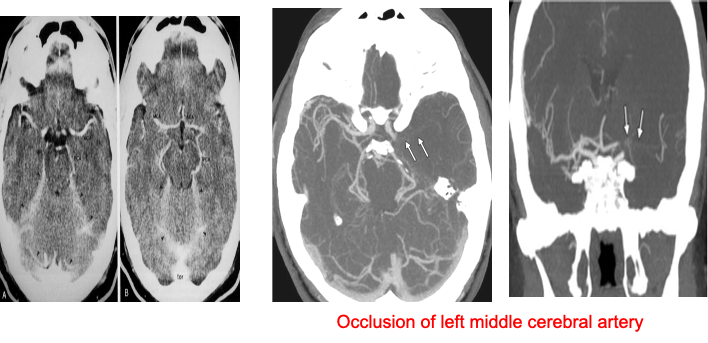

CT angiography (CTA)

is helpful in diagnosis of vascular diseases and abnormalities such as stenosis, occlusion or vascular malformation